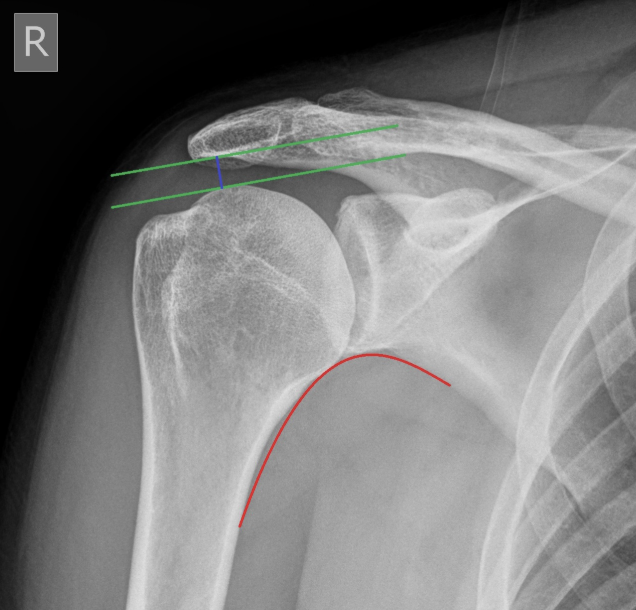

What is the most important arch in shoulder XR?

Moloney’s arch